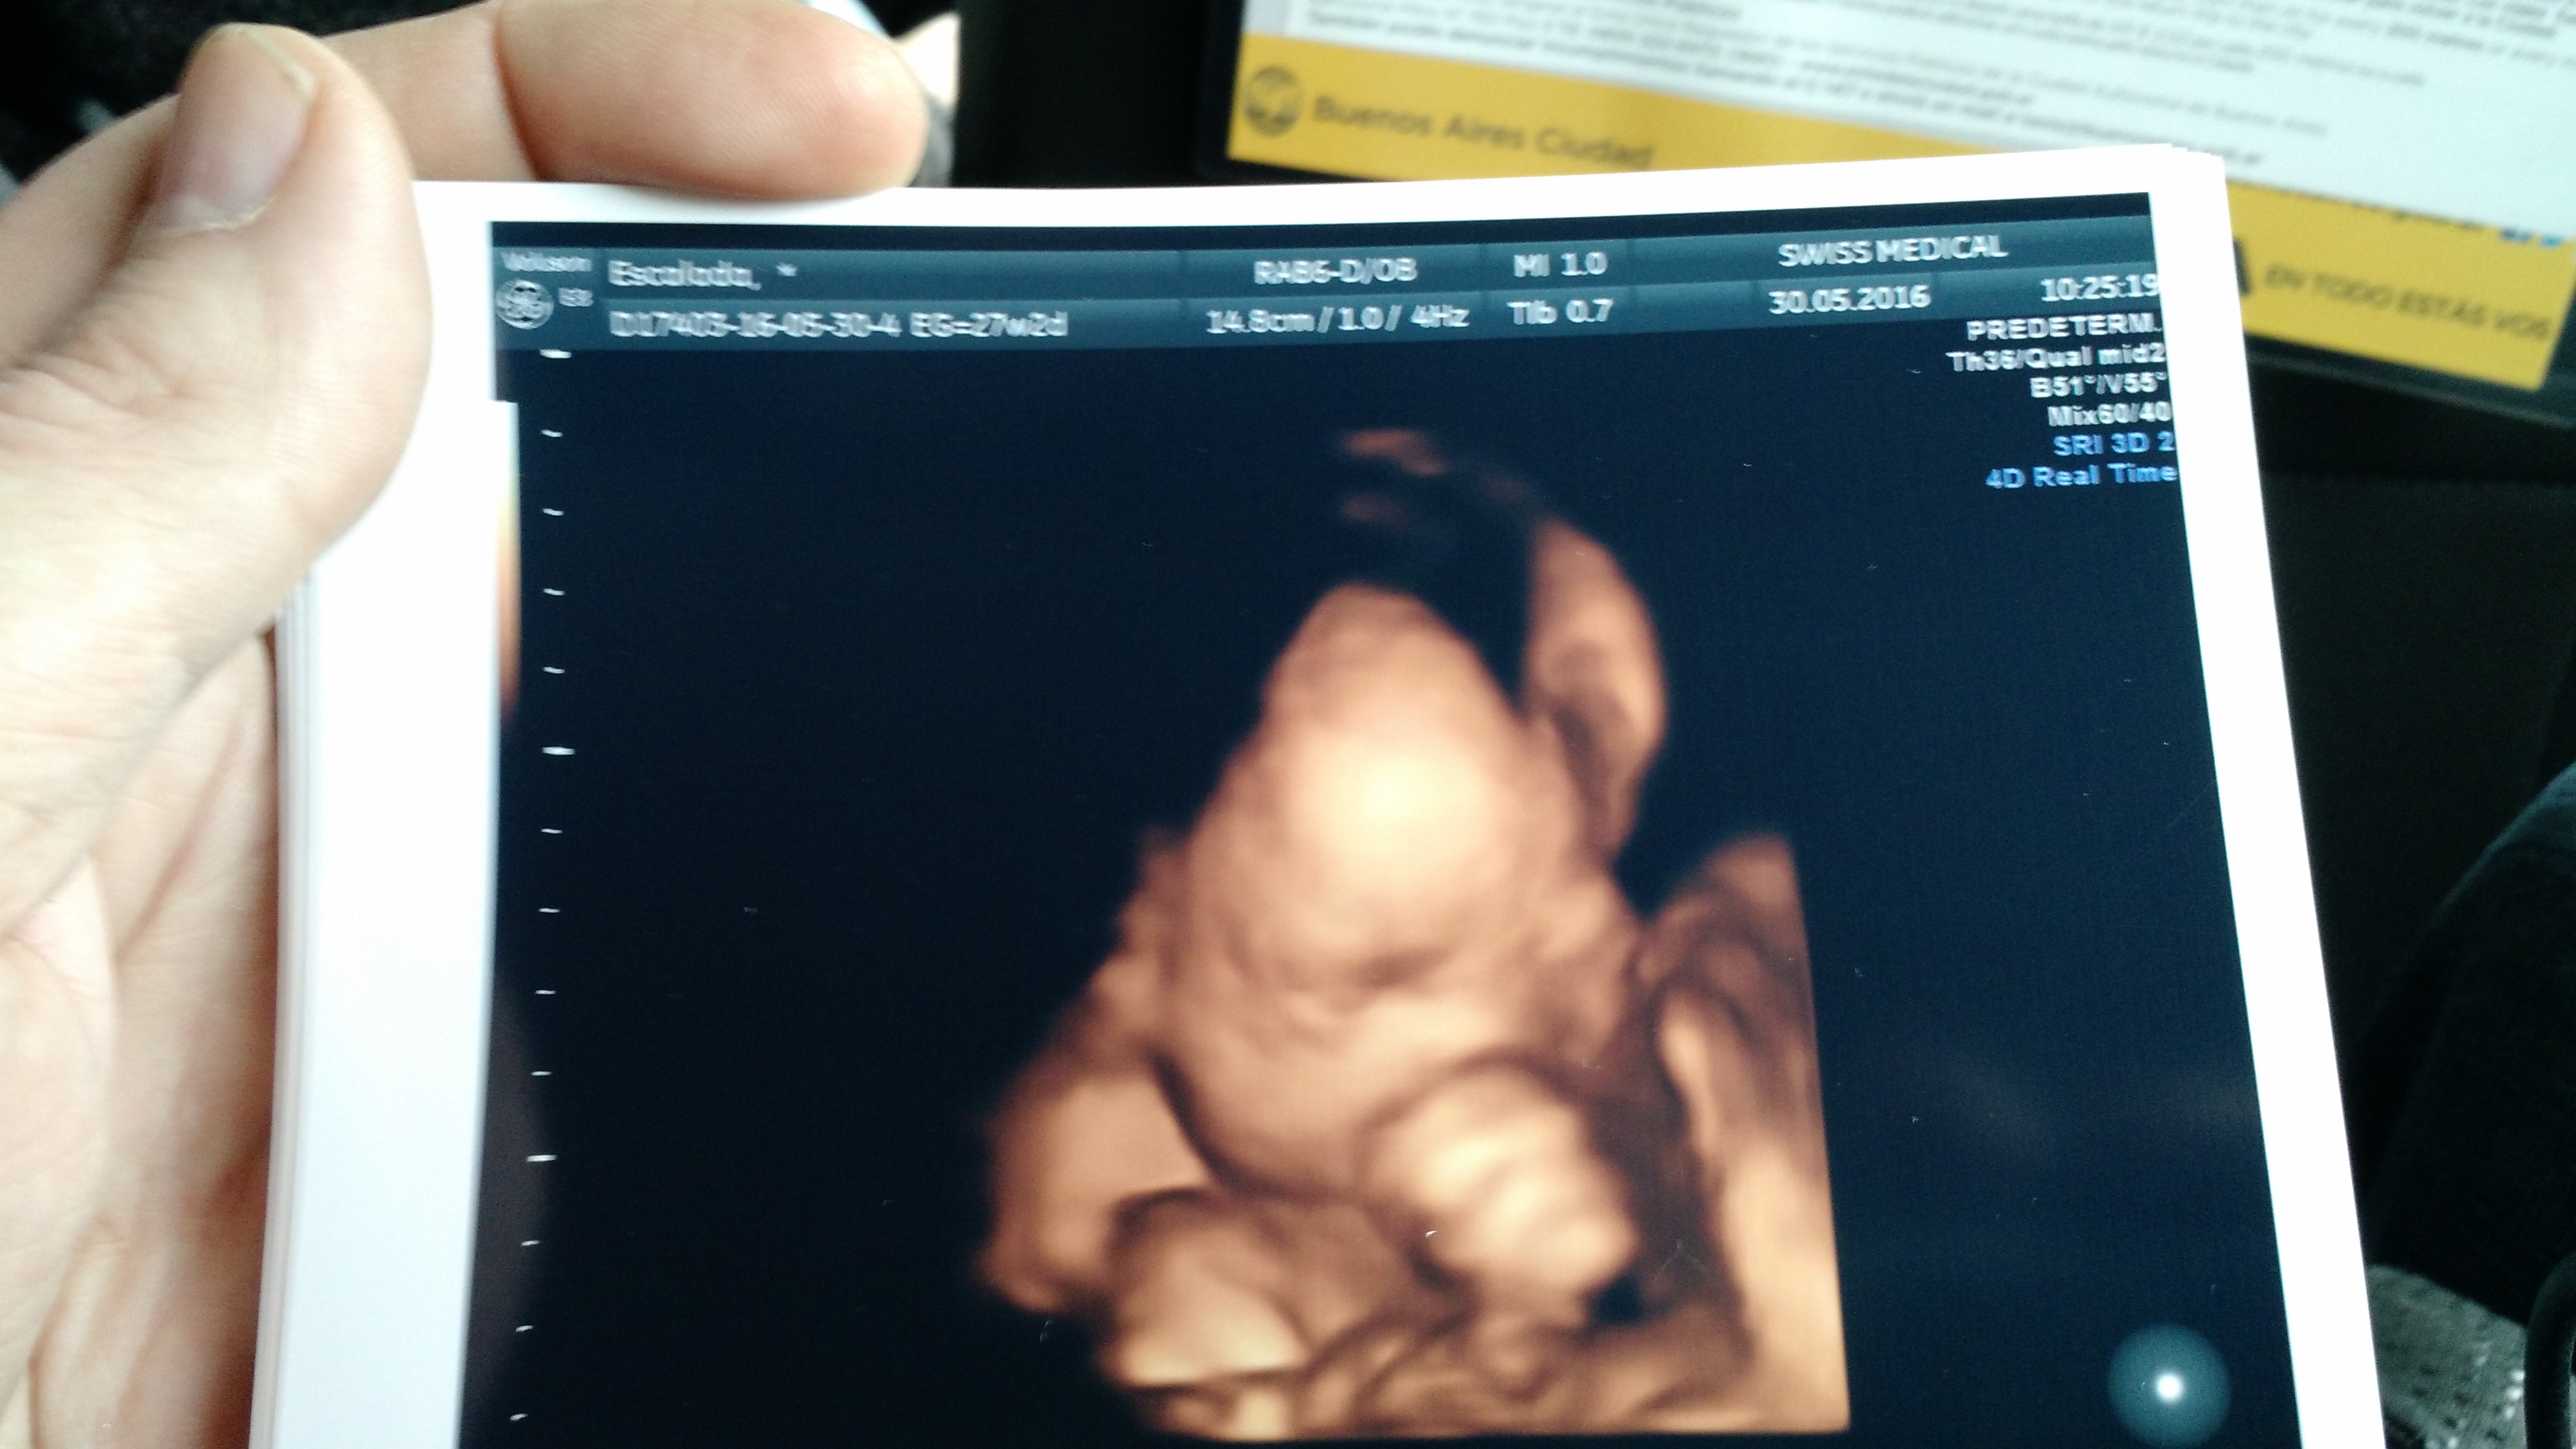

Y llegó también el último control: Andrea siempre lo recordó toda su vida por un grito mío: «Le veo la carita! es hermosa!»

En la última resonancia de repente pude ver cómo la imagen se aclaraba y su rostro se me revelaba: pude verle un instante clarita la carita a mi hija antes de nacer! Cuando saqué la foto ya no se veía más… y depués se empezó a chupar el dedo!